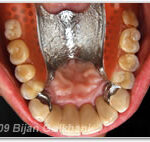

Amalgamfüllung